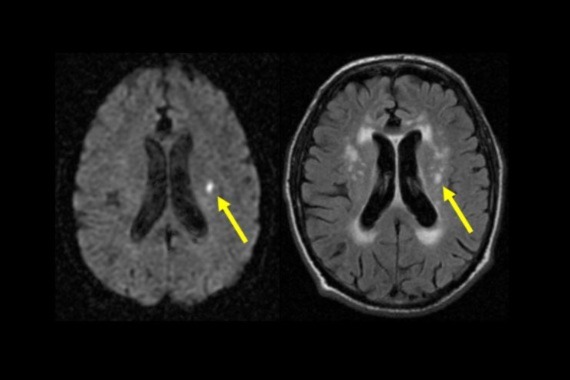

Image: Brain MRI scans with arrows indicating a lacunar stroke (with thanks to Professor Joanna Wardlaw for providing)

A stroke happens when there is an interruption in blood supply to part of the brain. Lacunar stroke is a type of stroke thought to be caused by cerebral small vessel disease (cSVD), where small blood vessels deep within the brain become damaged. It accounts for about a fifth of all strokes, with at least 35,000 lacunar strokes happening each year in the UK. They can lead to people developing problems with their thinking, memory, movement, and ultimately dementia - but there are currently no proven effective preventive treatments. Overall, cSVD is thought to contribute to around 40 per cent of dementia cases.